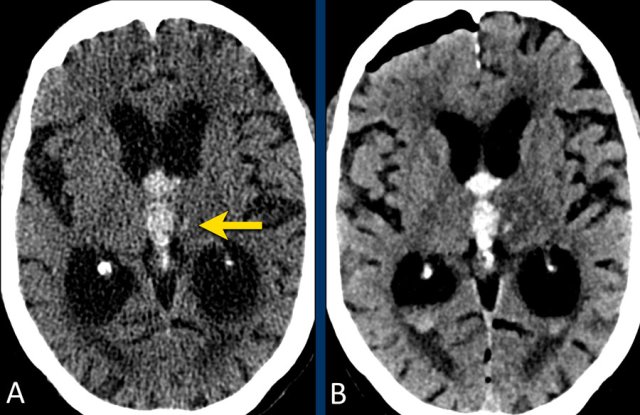

This patient was submitted to the stroke unit with a recent infarct in the left MCA territory.

Due to delay in presentation outside the thrombolytic window, no thrombolytic therapy was given.

A follow-up NECT (image A) was ordered because of clinically deterioration and showed a well demarcated hypodense area in the left MCA territory. In the hypodense area, very small subtle hyperdens foci were depicted.

MRI several hours later the same day showed foci of hemorrhage (arrow) indicating petechial hemorrhagic transformation of the ischemic infarct.